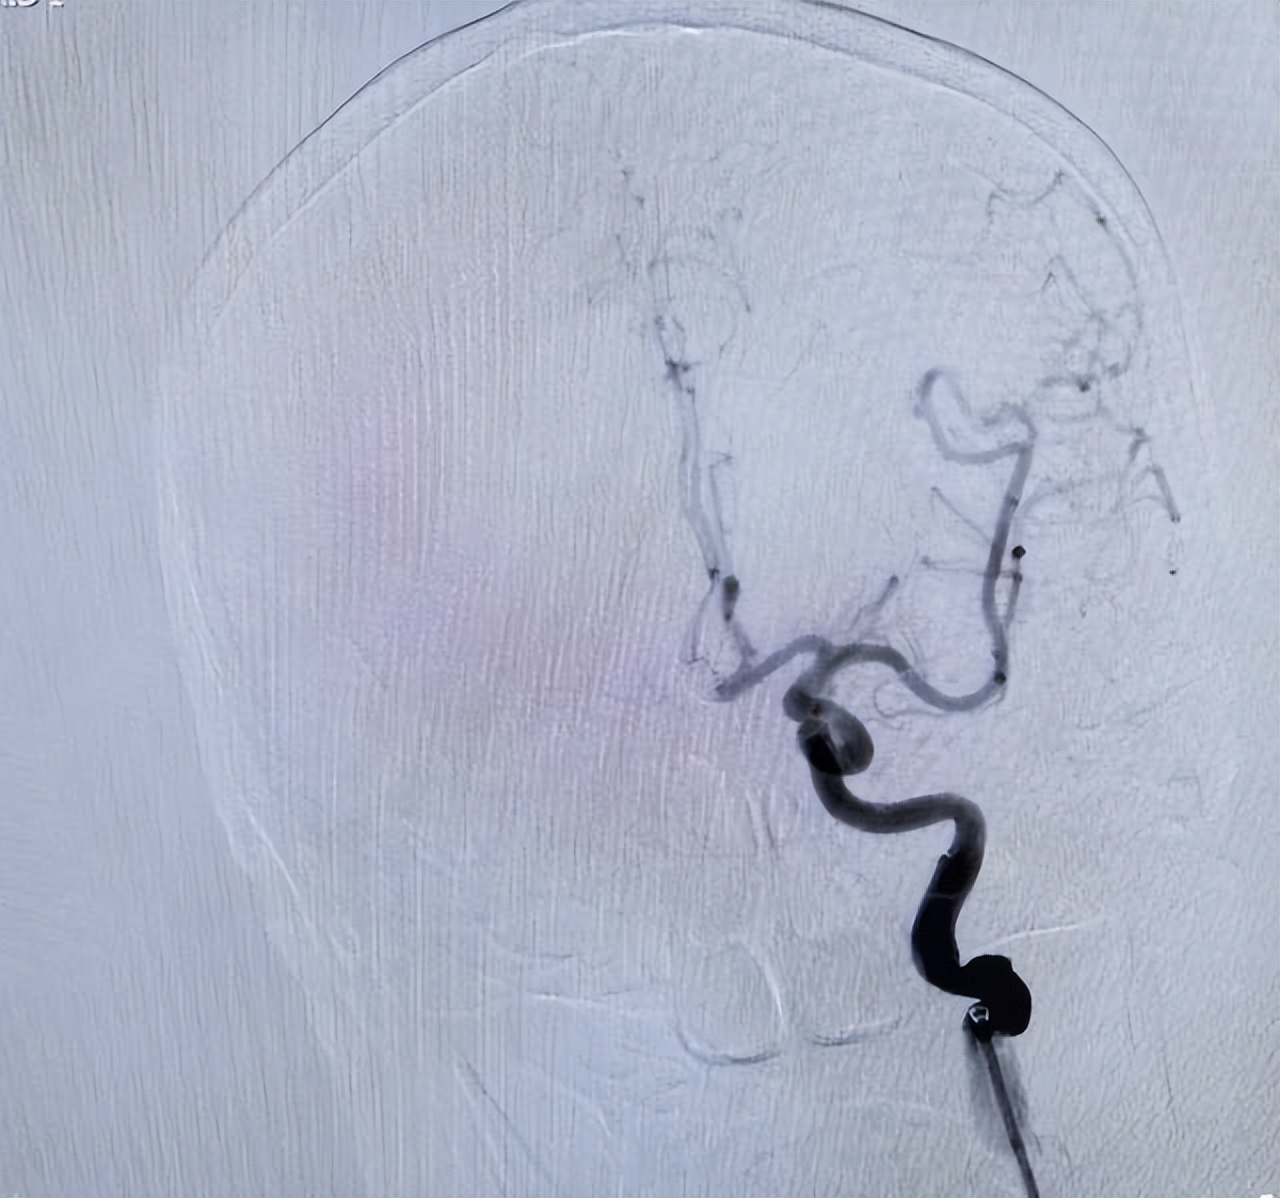

△术后影像

经过紧张的手术和术后监护,刘女士不仅挺过了难关,还顺利拔除气管插管,意识清醒,言语流利,肢体活动自如! 从命悬一线到转危为安,这场生死救援,见证了安居区人民医院卒中中心多学科协作的硬核实力,更彰显了医护团队“不放弃每一丝希望”的医者担当!此例动脉瘤栓塞术的成功实施,标识着安居区人民医院脑血管治疗领域实现全面突破。